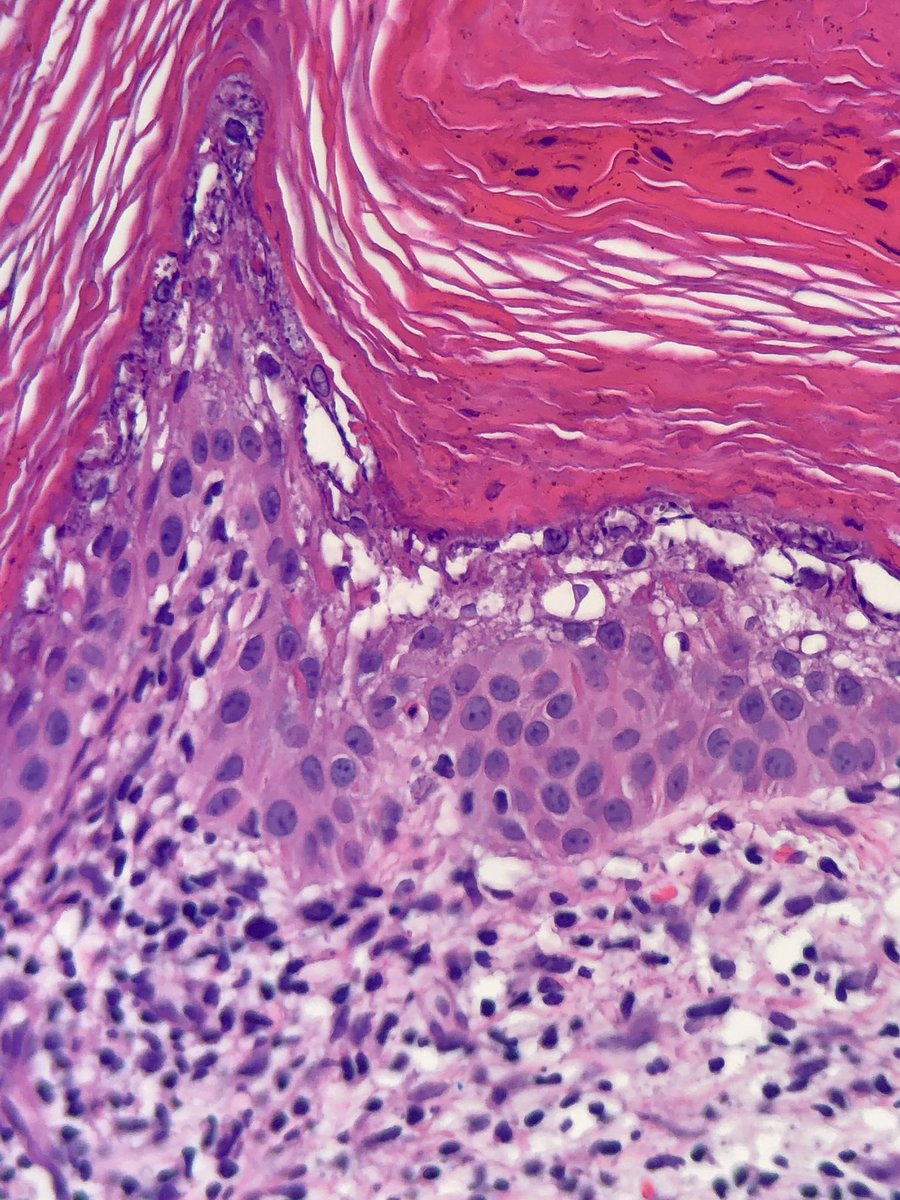

Upper arm. Older patient. @HENRYY_MD you’re only allowed to look at the low power image. Others can look at the high power. @et565 @forthejon @ZachHopkinsMD @DrGeeONE #anyoneelsecananswer #pathology

English